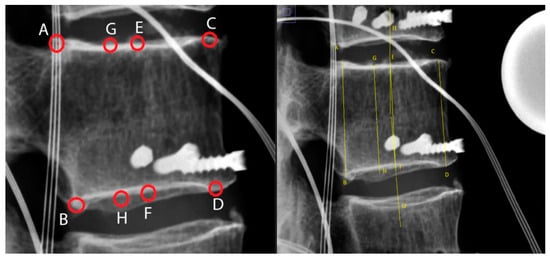

2.5. Radiological Assessment

3.1. Fracture Creation and Vertebral Body Reconstruction